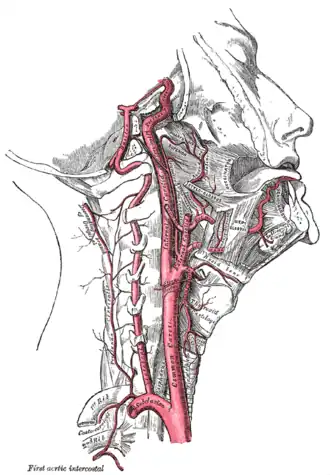

| Artery | Buccal artery |

The internal carotid and vertebral arteries, right side

The internal carotid and vertebral arteries, right side -